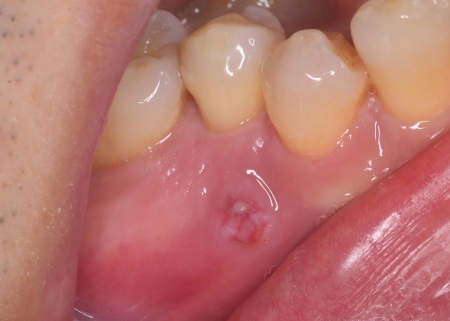

| 主訴 | 「右下の歯ぐきが腫れているのが気になる」とご相談いただきました。 |

| 診断 | 拝見したところ、右下奥歯の根元の歯ぐきに腫れが見られました。 原因を調べるためにレントゲン検査を行ったところ、歯の根の先に炎症が起きている様子が確認できました。 さらに詳しく調べた結果、歯根の壁に穴があくパーフォレーションが起きており、その穴から細菌が入り込んで歯根の周囲に感染と炎症が広がっていると考えられます。 パーフォレーションとは、歯の内部にある神経の通り道と歯の外側を隔てている壁に穴があいてしまう状態のことです。 このまま放置すると、炎症がさらに広がり歯を残すことが難しくなる可能性があることから、できるだけ早めに処置を行う必要があると診断しました。 |

治療前